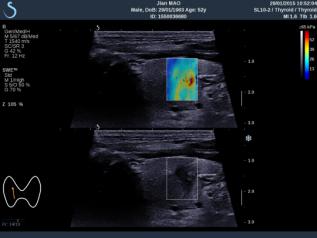

E成像(SWE)實時剪切波彈性成像技術(shù)

“聲藍”獨有的E成像(SWE)實時剪切波彈性成像技術(shù)可以廣泛應(yīng)用在實性臟器腫瘤的早期檢出和鑒別診斷、定量評估、介入穿刺引導(dǎo)、各類疾病治療前后的評價等,也是唯一全面通過美國FDA認證的實時、全幅、全定量的組織硬度可視化測量模式,因而為臨床診斷和治療,提供了安全、無創(chuàng)、有效的最新影像學全新檢查方法。目前已被應(yīng)用于甲狀腺、乳腺、肝臟、腎臟、前列腺、腸管、淋巴結(jié)、肌肉骨骼、軟組織等全身器官的鑒別診斷和定量評估。

彈性超聲與以往普超聲相比,相當于“深觸診”,可以更加直觀地“接觸到”軟組織的形態(tài),并且速度可達到1厘米/秒。與此同時,它的畫面是連續(xù)性的,具有以往單點式的超聲設(shè)備無可比擬的優(yōu)勢。它的“彈性”級別也是最高的,特別適應(yīng)于甲狀腺和乳腺的超聲診斷,并且配備了多個探頭,適用于人體不同部位的超聲需求。彈性超聲的引進與應(yīng)用,可對腫瘤的良惡性鑒別診斷及肝纖維化的無創(chuàng)診斷提供重要依據(jù),可明顯提高診斷準確率,具有非常高的敏感性、特異性,提高檢出率,為臨床診斷及治療提供重要依據(jù),盡早為患者爭取最佳的治療時機。